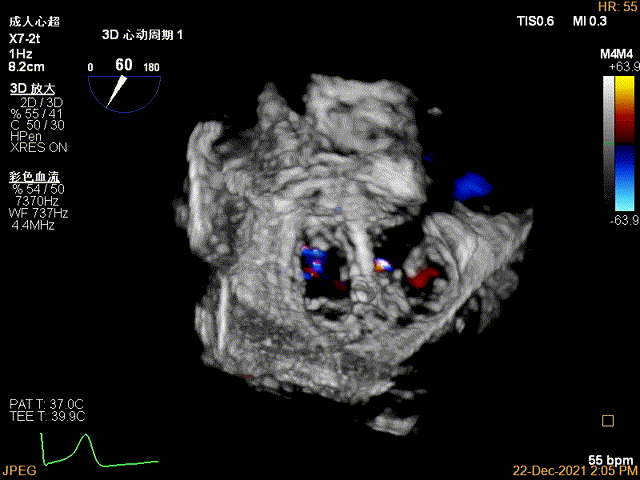

3D MV View:P2区脱垂

3D-color MV view:大量反流,起源于2区

3D视图穿刺点位近似于3点位

3D视图下开夹子

3D视图下调整夹子位置及Rotate,第一个夹子放置于靠近内侧区域

3D视图下夹子对准最大反流束进入左室

3D-VIEW验证前后叶抓捕情况,可观察到第一个夹子外侧的残余脱垂

3D-color-VIEW验证残余分流,位于第一个夹子外侧

3D-VIEW提示第二个夹子置于第一个夹子外侧,并呈平行关系

抓捕外侧残余脱垂瓣叶

3D-VIEW验证抓捕结果

3D-color-VIEW验证残余分流近消失